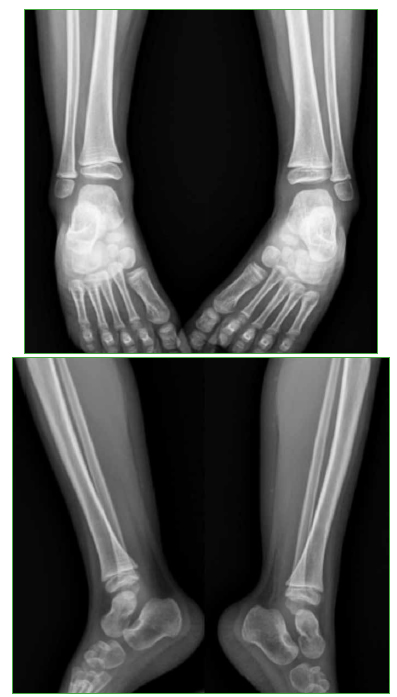

Clínicamente la paciente mostraba facie de dolor y llanto a la palpación del tercio distal de la pierna. Sin dolor a la movilidad pasiva del tobillo. No se observaron hematomas, edema, ni signos de flogosis local. Se solicitaron radiografías de ambos miembros inferiores, en las cuales se observó una lesión osteolítica que comprometía la metáfisis distal de la tibia izquierda (Figura 1).

Figura 1. Radiografías de frente y de perfil, de ambos tobillos. B y D. Se puede observar la lesión osteolítica en la metáfisis distal de la tibia izquierda.